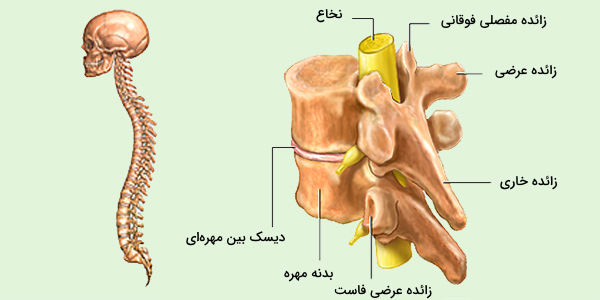

اسکلت جمجمه و گردن انسان ستون فقرات آناتومی اسکلت جمجمه و گردن انسان ستون فقرات آناتومی تصویر با کیفیت را از لینک زیر می توانید دانلود کنید. ۱ مطلب با کلمه ی کلیدی عکس اسکلت بدن انسان با کیفیت ثبت شده است گالری نسیم جدید ترین و با کیفیت ترین عکس های مناسبتی. عکس با کیفیت آناتومی اسکلت بدن انسان و درد و دیسک در قسمت مهره های ستون فقرات کمر ویژه استفاده در امور تبلیغاتی و تجاری طراحی کاتالوگ بروشور و تراکت با موضوع بیمارستان ها و کلینیک ها و درمانگاه ها و مطب ها پزشکان و.